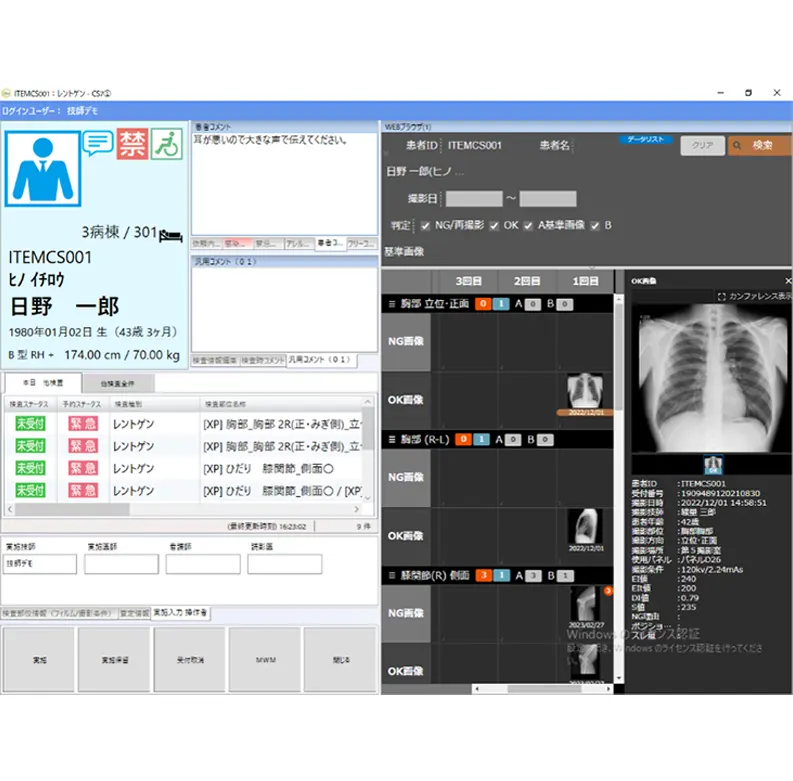

2. デジタルラジオグラフィー AeroDR swift/

画像診断ワークステーション CS-7

DQE59%(1mR,1cycle/mm)、画素サイズ100μm の高画質ながら半切サイズ1.9kg、17×17 インチサイズ2.3kg (ともにバッテリー込み重量)を実現した「AeroDR swift」。ハンドリングの良さでX 線撮影作業時の負担軽減と運用改善に寄与します。「CS-7」では、業務支援AI:ポジショニング判定支援機能「Positioning-i」を中心とした再撮影削減の取り組みを紹介します。「再撮影」という臨床現場での課題解決に向けたサポートを提案します。

5. 一般撮影新ワークフロー

RAD Link(ラドリンク)

新ワークフロー「RAD Link」により、一般撮影検査前の過去画像確認の運用を改善し、撮影の効率化を図ることができます。当該患者の過去写損画像や施設基準画像を弊社の一般撮影コンソール「CS-7」上で簡単に参照可能なため、撮影開始前に留意すべき点を事前に把握でき、不要な再撮影を削減することができます。検査の再現性を向上し、写損率を減少することで効率的な業務を推進、診療放射線技師の働き方改革にも繋がるシステムです。